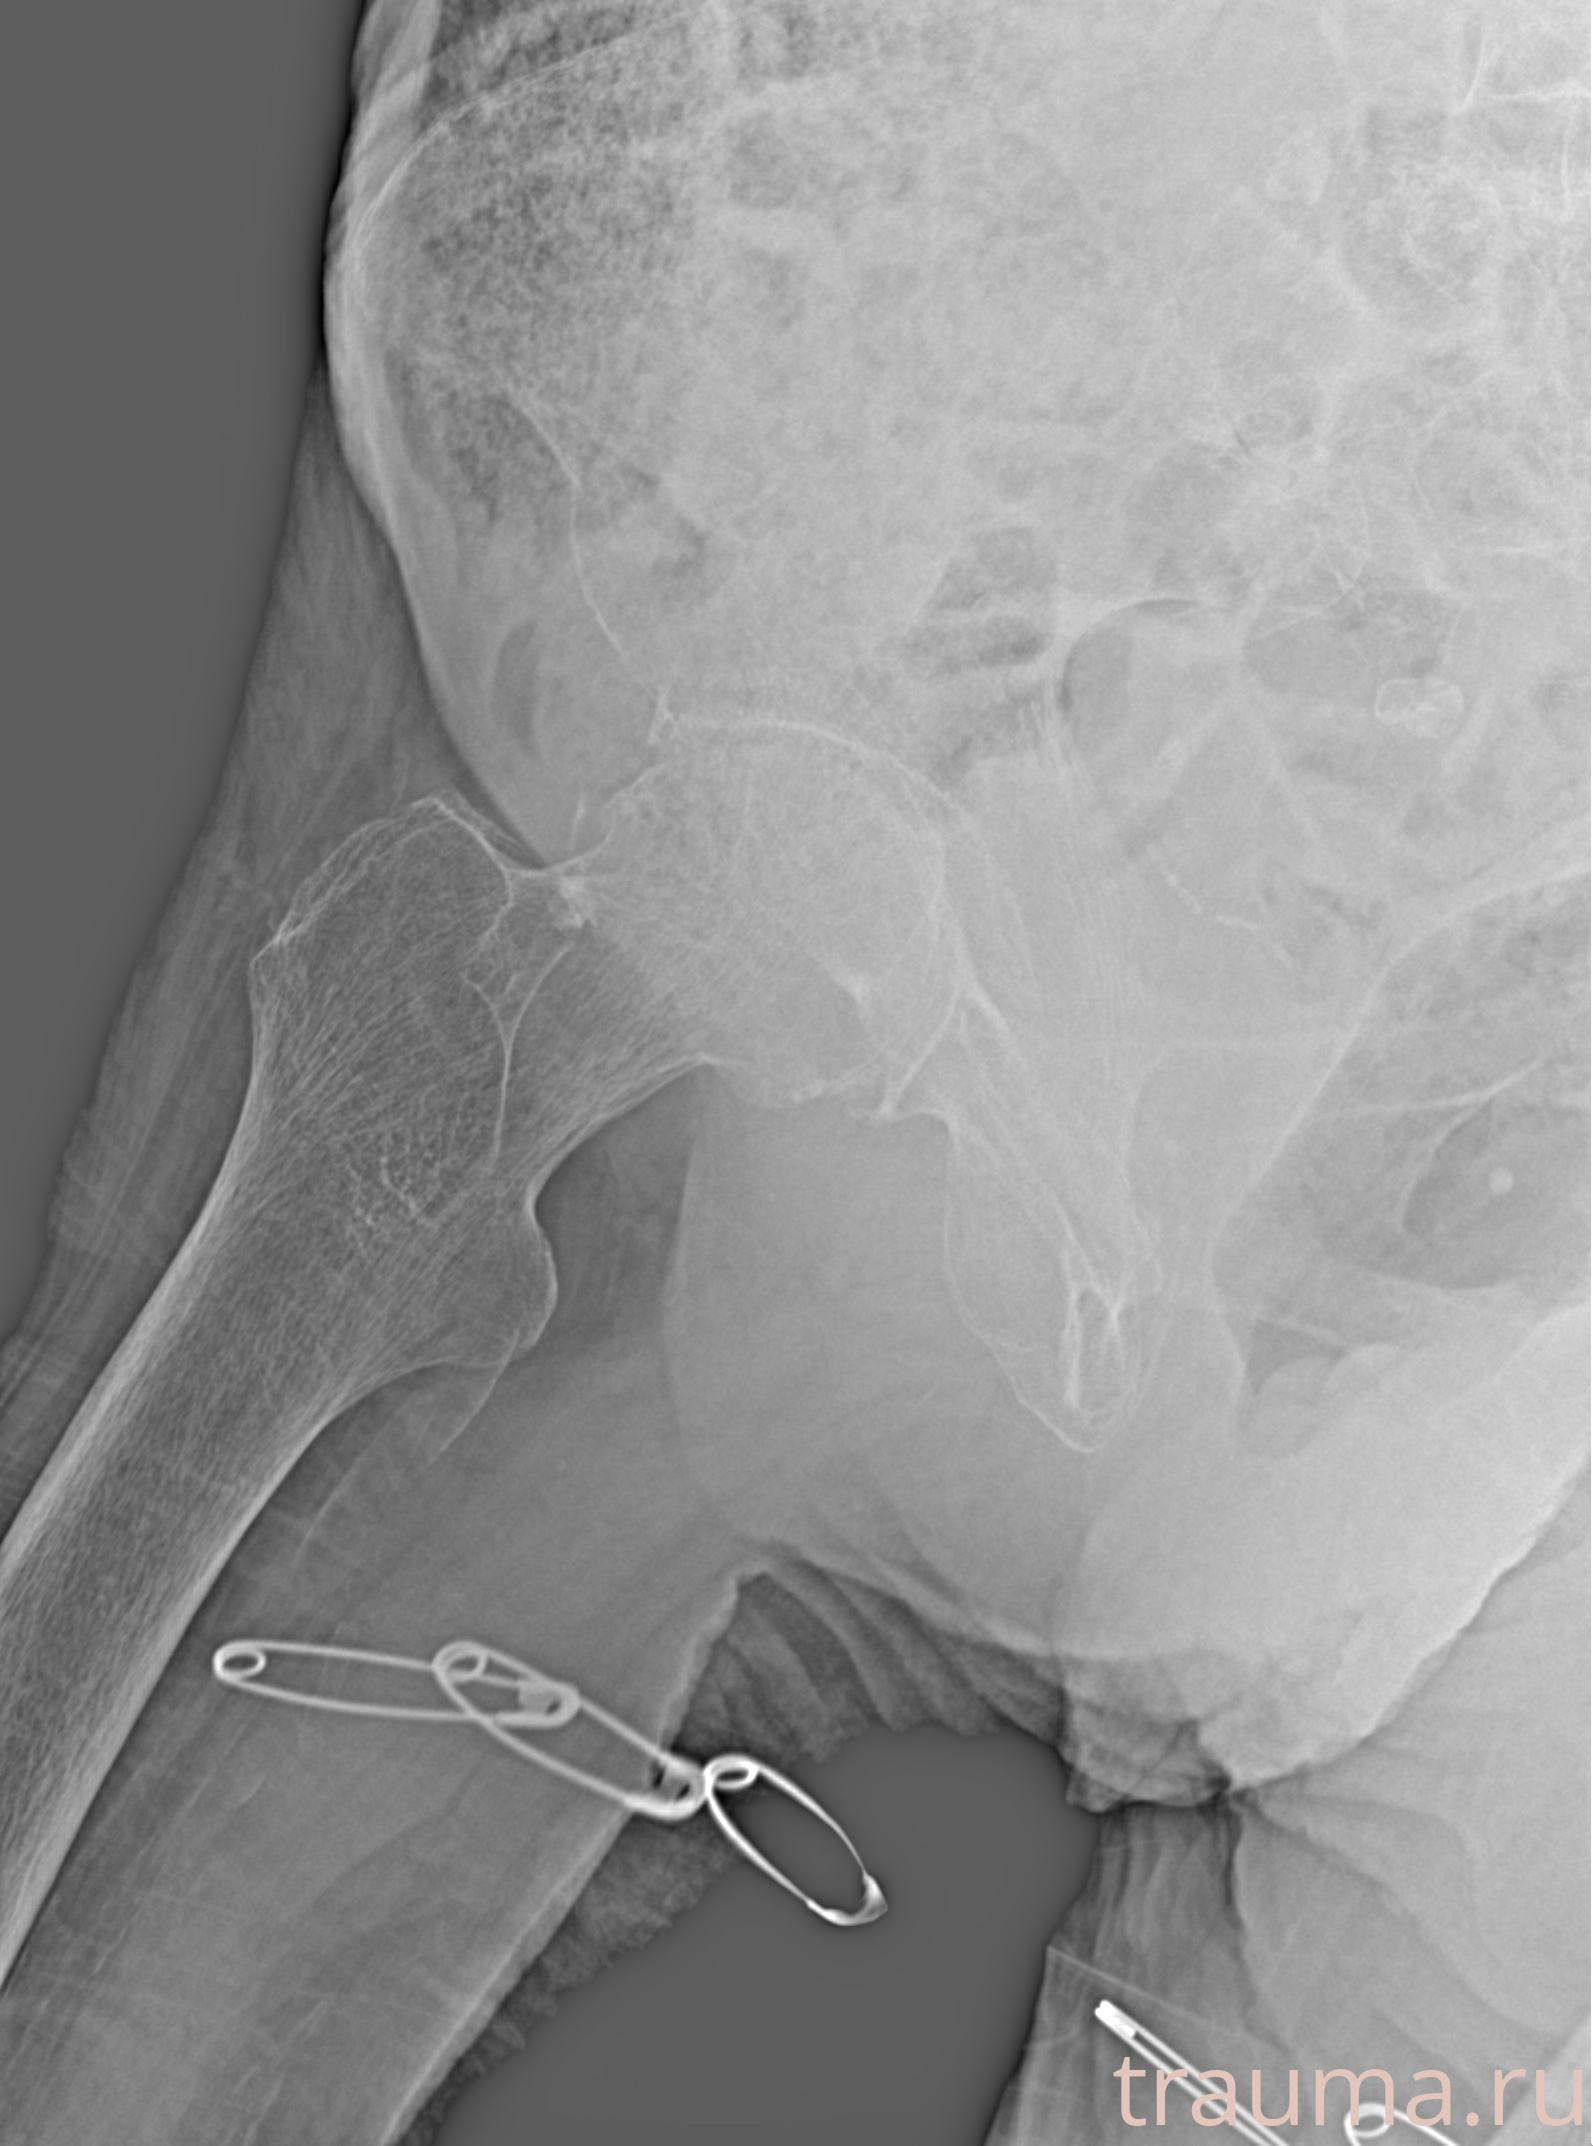

Рентгенограммы

Рентген на дому: по вашему адресу приезжает врач-рентгенолог, травматолог-ортопед с мобильным рентгеновским аппаратом, проводит диагностику травмы или заболевания, делает необходимые рентгенограммы, дает рекомендации по дальнейшему лечению. Получить качественные снимки в домашних условиях возможно благодаря уникальной методике, разработанной МосРентген Центром для института  Склифосовского